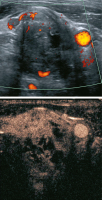

Abbildung 1: Normalbefund, intranodale Gefäßarchitektur. Normalerweise sind die Lymphknotengefäße baumartig vom Hilus ausgehend. Die Verästelung ist regelmäßig. Die Gefäße sind am Außenrand des Cortex so klein, daß sie mit Farb- und Powerdoppler (derzeit noch) nicht erkennbar sind. In diesem Fall ist die Gefäßzeichnung nur minimal verstärkt im Rahmen einer infektiösen Mononukleose.